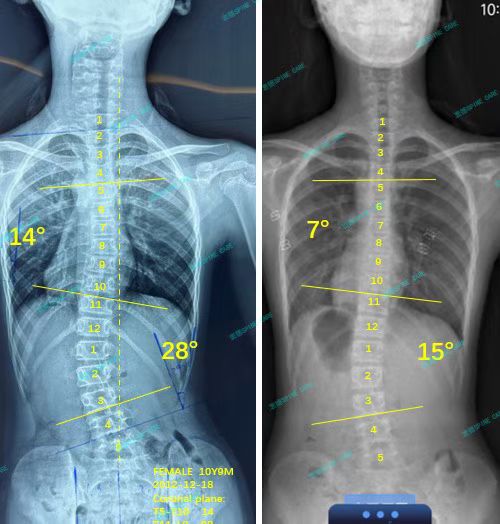

来自家长对衷德的评价(甜甜妈妈)